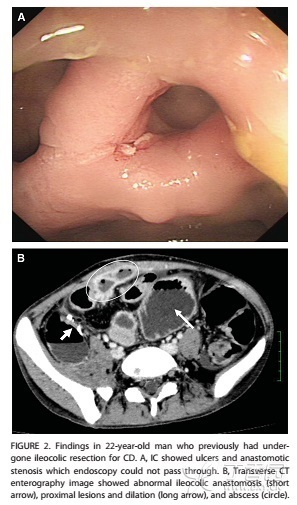

一名22岁接受回结肠切除治疗的克罗恩病男性患者的检查结果。

A.为内镜结果,显示溃疡形成,吻合口狭窄,内镜无法通过。B.为CT扫描肠造影结果,显示异常回-结肠吻合,近端回肠病变扩张、脓肿形成。